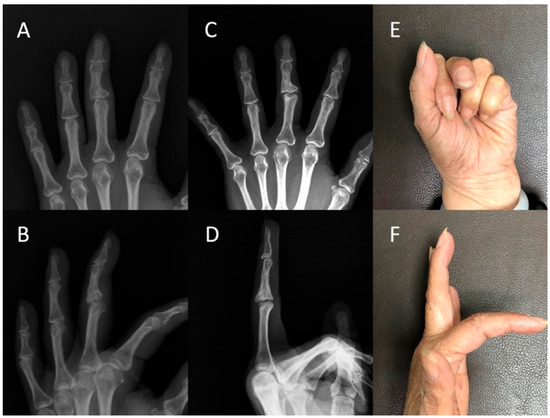

Figure 3. Case #5: A 33-year-old man developed post-traumatic osteoarthritis of the left ring finger. Radiographs of the left ring finger in the (A) anteroposterior (AP) view and (B) lateral view revealed post-traumatic osteoarthritis of the proximal interphalangeal joint in the preoperative status. The six-year follow-up assessment revealed preserved joint space in the (C) AP and (D) lateral views. The active flexion of the finger was 90° (E) with no extensor lag (F).